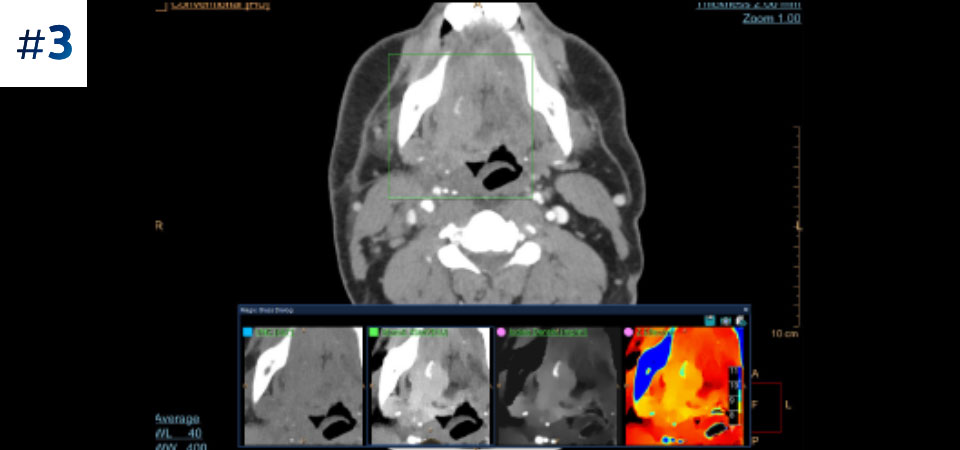

Guz szyi

Większe możliwości w zakresie badań kardiologicznych dzięki obrazowaniu spektralnemu pełnego pola widzenia. Redukcja artefaktów powodowanych przez uwapnienie tętnic wieńcowych.

Ograniczenie liczby ponownych badań Udoskonalona charakterystyka i wizualizacja tkanek może ograniczyć konieczność wykonywania ponownych badań, jaka zachodzi w przypadku badań o niezadowalającej jakości oraz przypadkowych obserwacji.

Typowy przebieg badania Pojedyncze skanowanie zapewniające szybki dostęp do konwencjonalnych i spektralnych danych uzyskanych z użyciem niskiej dawki — za każdym razem i w przypadku każdego pacjenta.